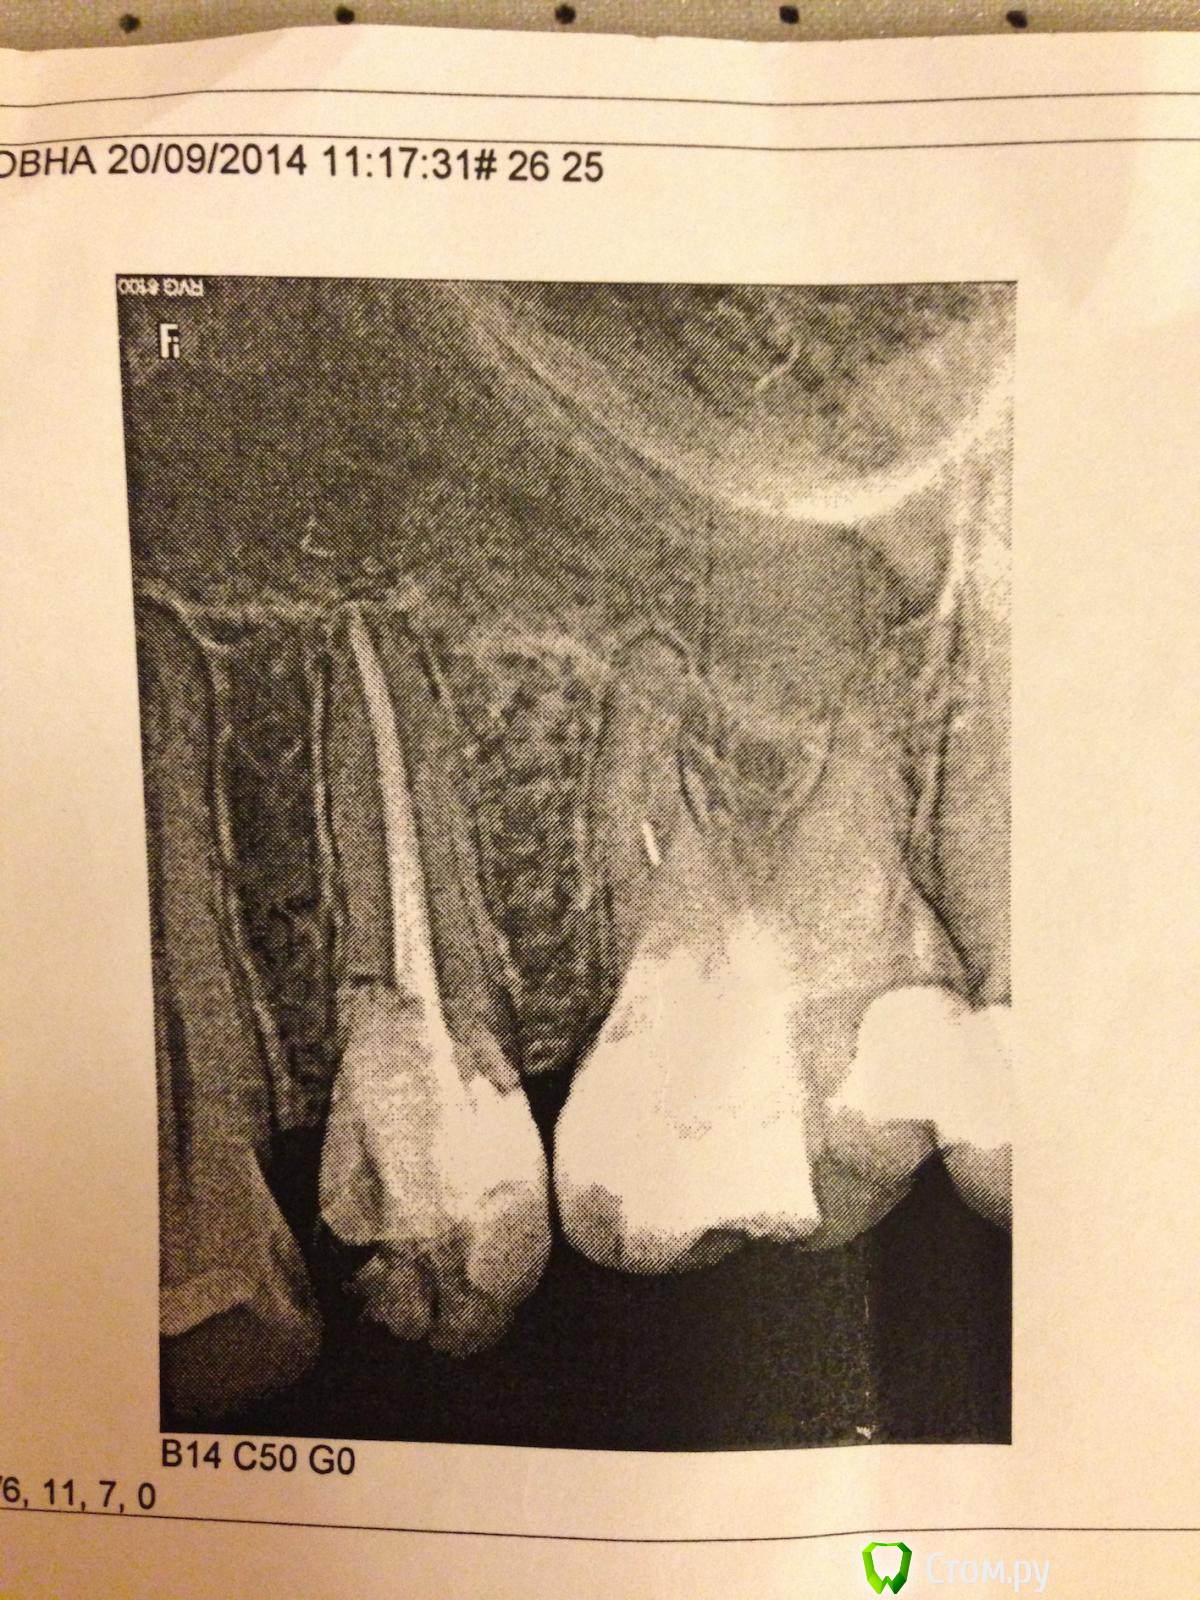

Остаток инструмента в зубе

На пятый день- боль не стихала. И я обратилась в другую стоматологию. Сразу сделали снимок.

Фото с распечатки прилагаю.

Стоматолог 2 предположила что в канале обломок инструмента и возможно есть трещина в пятерке. Она открыла зуб опять,  опять прочистила, что могла и оставила зуб открытым (знаю, что это плохой вариант). Боль, к сожалению, не прошла.

Если на 5-ке перелом (красный овал) прогноз для зуба неблагоприятен.  По поводу 6-го, если извлечь остаток инструмента(зелёная стрела) из канала, то после лечения всё с зубом будет в порядке. Как выложить скрины из КТ см. инструкцию на форуме.

Обломок инструмента (который вы пометили зеленым) вчера вытащили, я сама его видела. Доктора- просто чудесники и ювелиры. Этот канал очень тонкий и узкий прошли до конца.

Но, видимо, в недобрый час я пошла лечить зубы((((( При повторном снимке вчера, когда проверяли все ли хорошо с этим каналом, где был инструмент, на дне другого канала ( то есть на самой верхушке корня) увидели пару витков спиралей другого инструмента.  :blink: